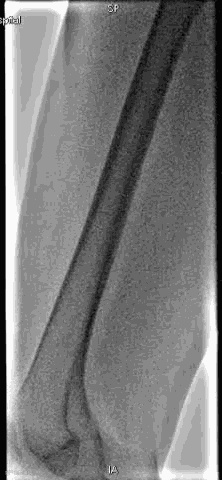

手术过程

抽吸结果